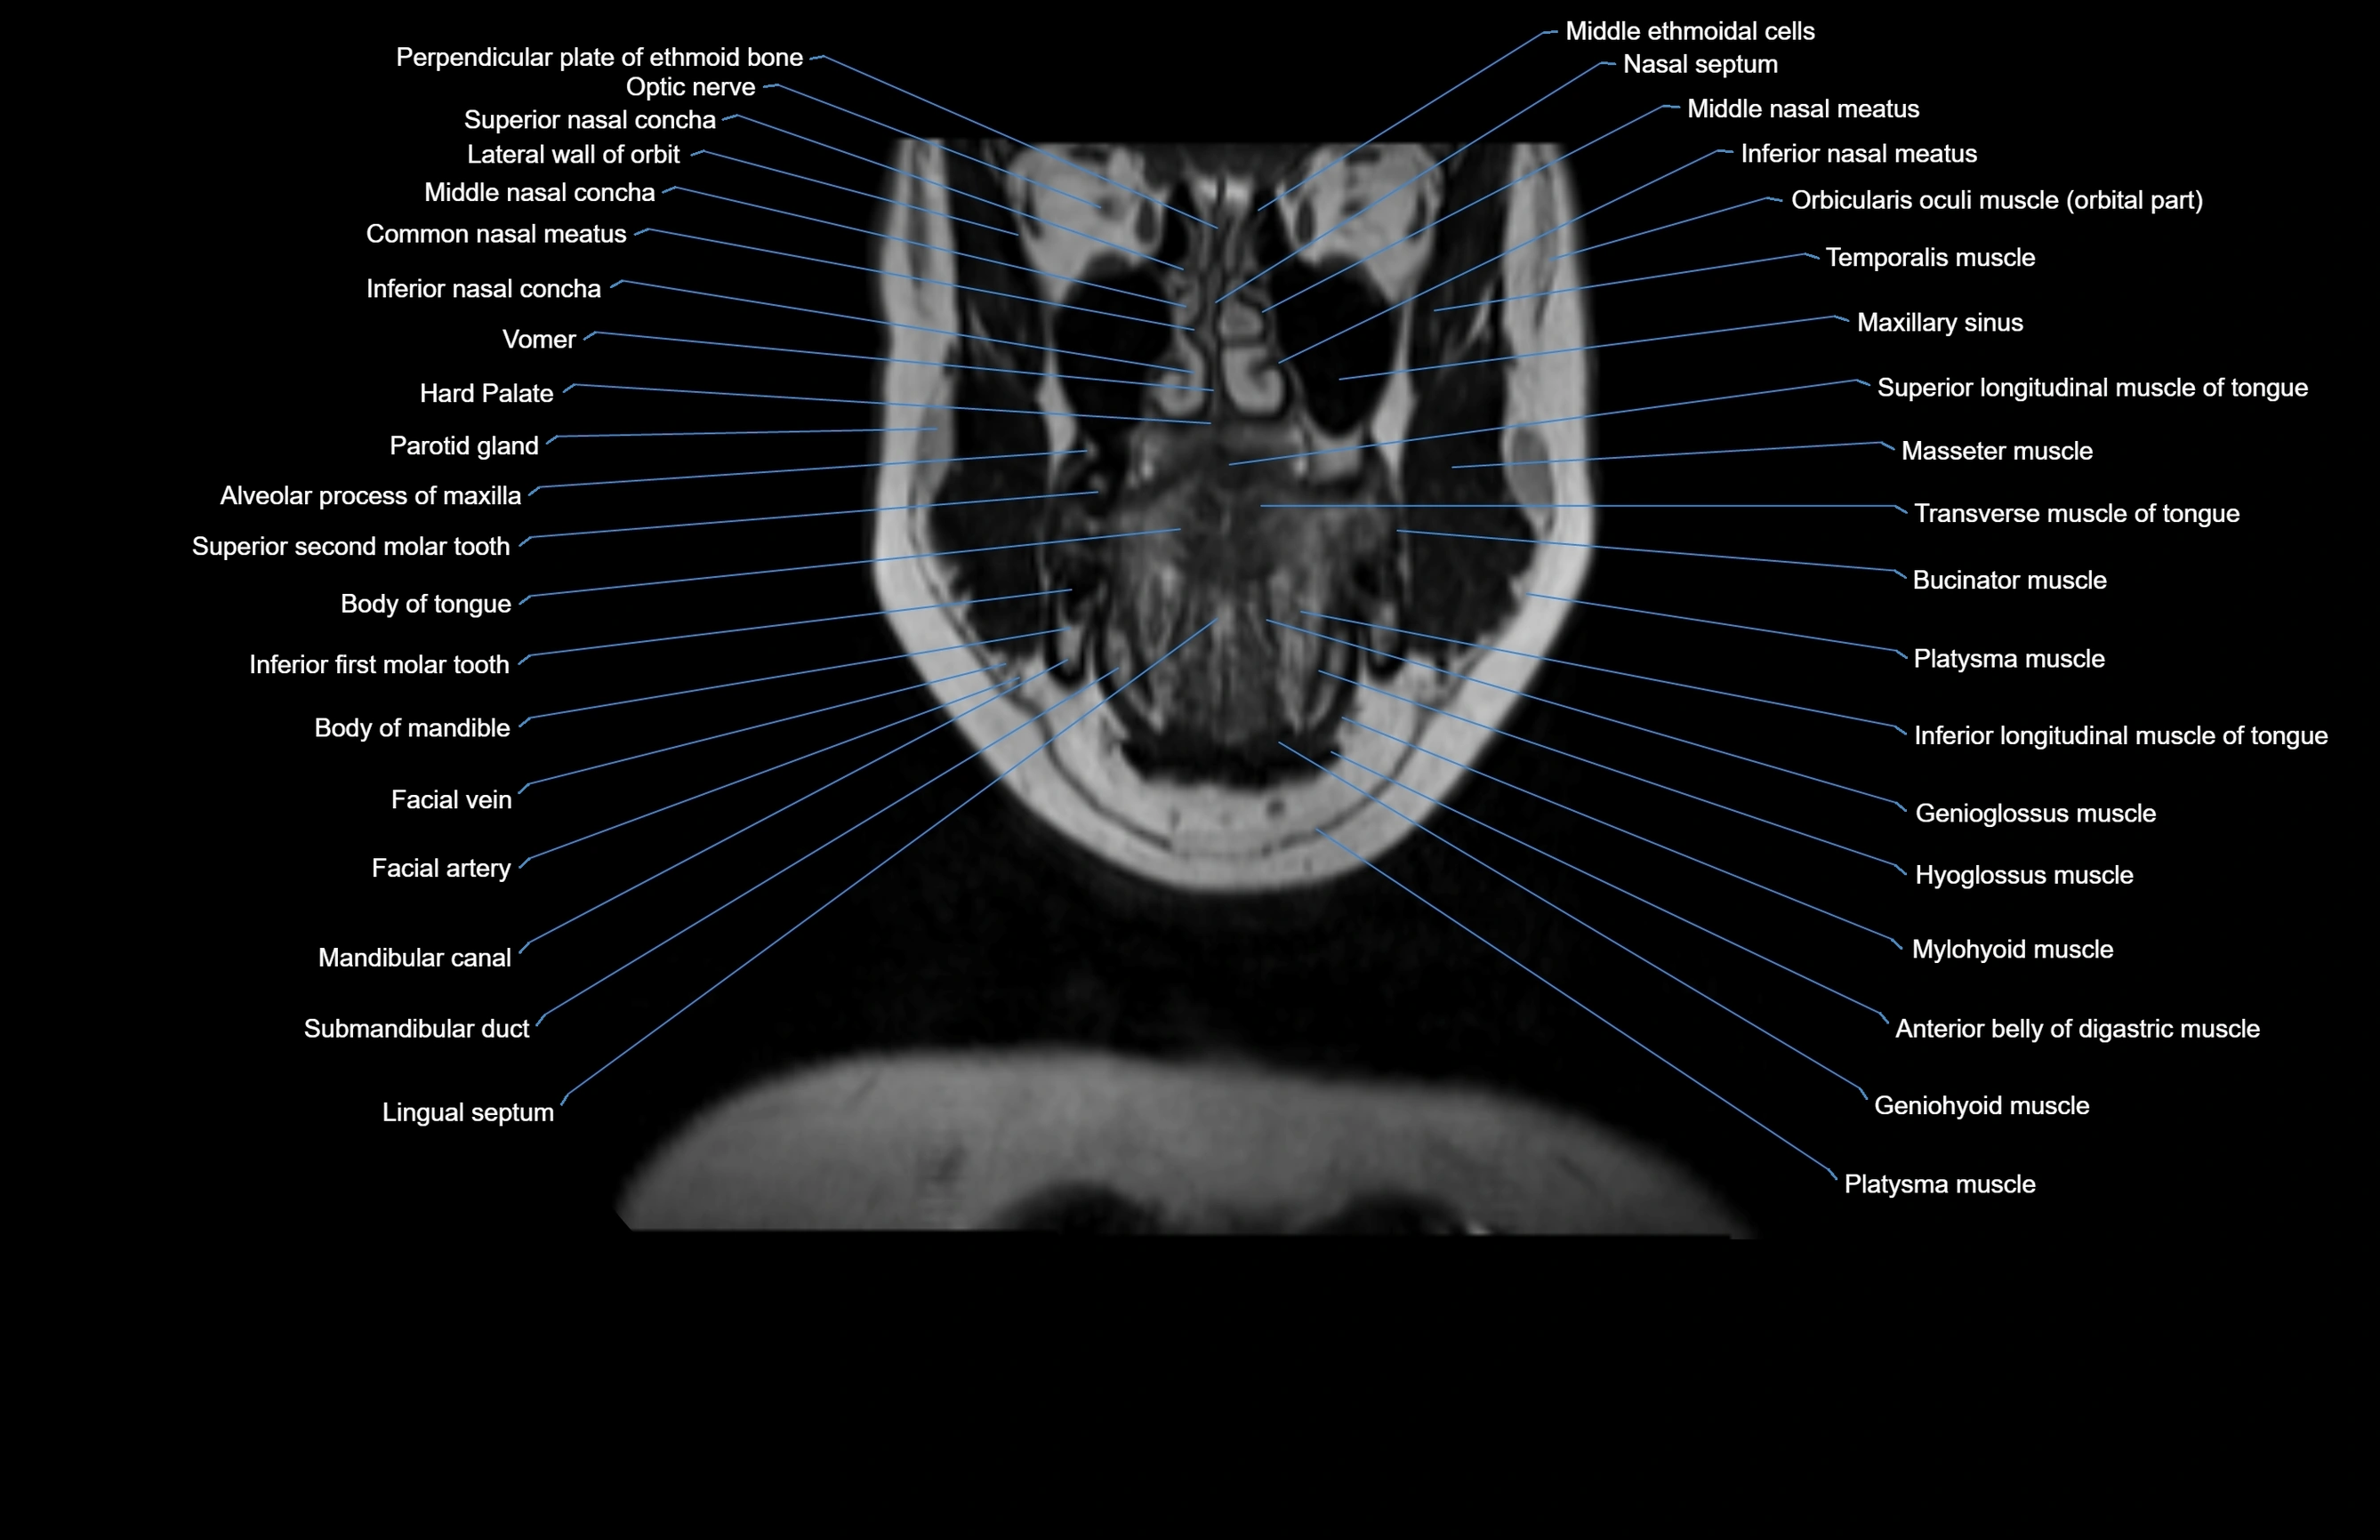

MRI images